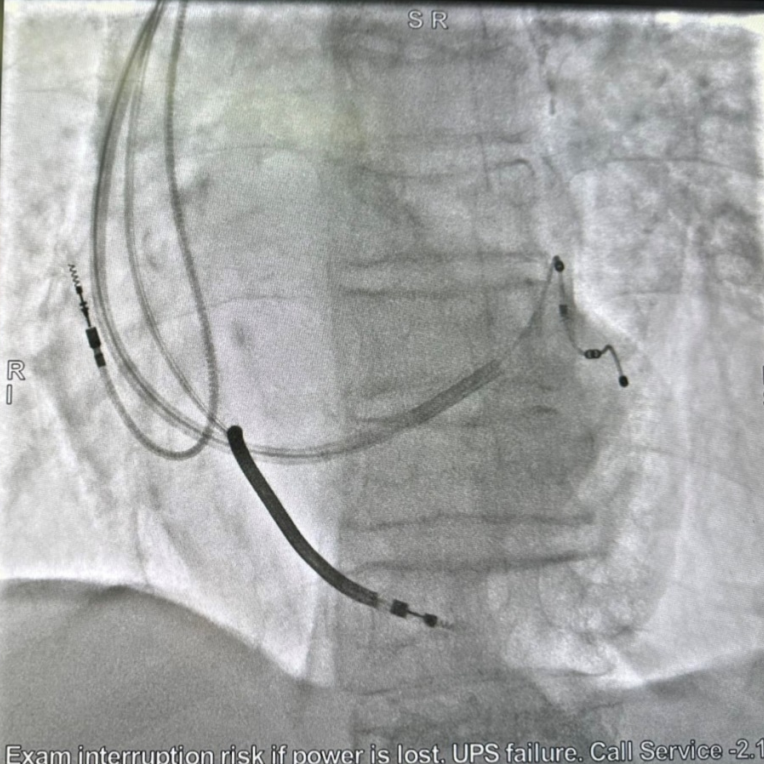

术中,造影显示患者靶血管迂曲,这使得传统左室电极放置脱位的风险明显增高。经汤宝鹏教授、张疆华主任医师现场评估,团队决定使用新型主动固定四极左室电级导线(ASQ),将电极主动固定在左室血管理想部位。手术全程仅一个半小时,术后测试各项参数良好,患者心电图显示其QRS波由术前153ms改善至术后89ms,各项症状也得到明显改善。